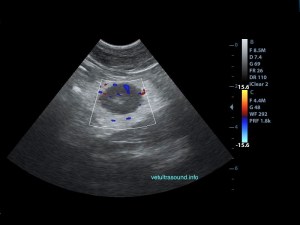

The spleen was increased in size with a diffuse parenchymal hyperechogenicity. A small section of the small intestine was enlarged with loss of its normal wall layers (pic1). The surrounding fat tissue was also hyperechoic. An enlarged regional mesenteric lymphnode was noted with diffuse hypoechogenicity. A Fine Needle Aspiration was performed in order to collect cytology speciments from the spleen and the intestinal lesions. The diagnose was alimentary tract lymphoma.